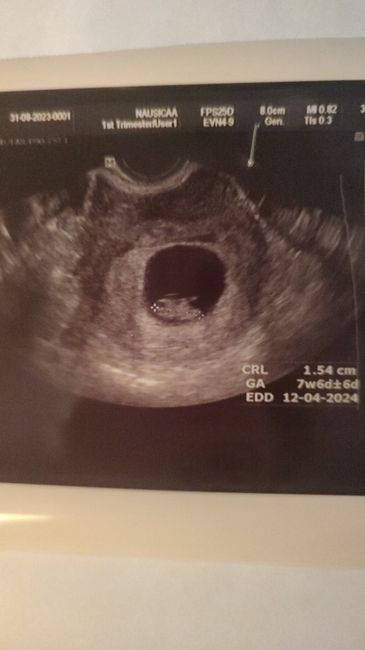

Faccio le beta ed erano a 14 (penso che come é iniziata sia finita).Invece dopo due giorni 54, dopo altri 4 giorni 380, altri 4 2860.A 8+5 ho fatto la prima ecografia, e ho ovulato tardi, infatti le misure erano di 7+6.Oggi sono a 8+4, e spero che questa volta vada tutto bene